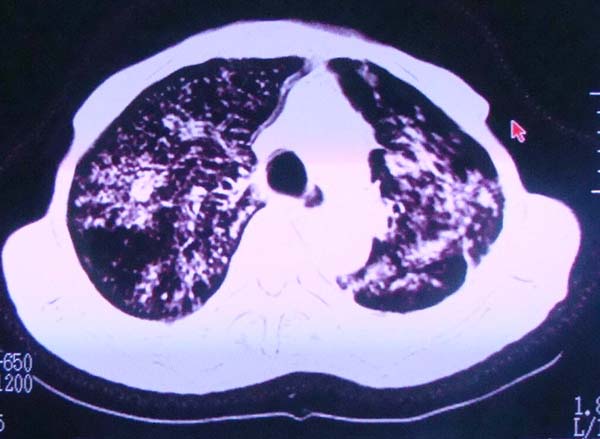

以下是引用zhangzhongshou在2008-2-15 22:25:00的发言:[br]片子照得不清,基本考虑1、细支气管肺泡癌2、亚急性血行播散型肺结核。请结合临床。片子细节显示不清,无法提供进一步意见。

以下是引用杀毒软件在2008-2-15 22:34:00的发言:[br]小叶中心性肺气肿。两肺弥漫性病变,肺泡微石病,过敏性肺炎,尘肺2期,特发性肺纤维化都有可能。[br]不象肺泡癌。